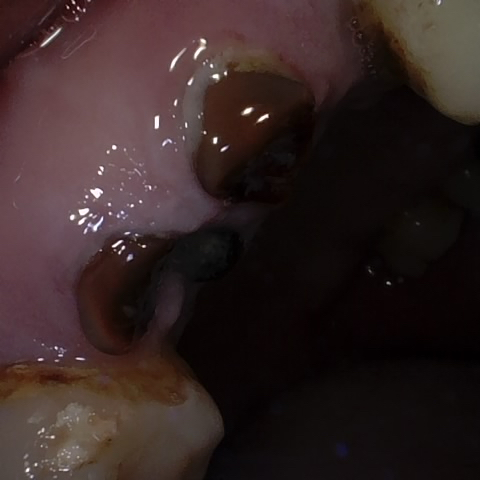

Incorrect Quality Level

The reference annotation for this image is

None

.

Please select the correct quality level.

Image 72 / 1743

Annotated as "Good"